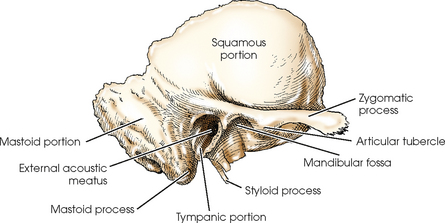

- Temporal Bone 1.Squamous 2.Petrous 3.Mastoid 4.Tympanic 5. ...

Temporal bone. The temporal bone is situated on the sides and the base of the cranium and lateral to the temporal lobe of the cerebrum. The temporal bone is one of the most important calvarial and skull base bones.

What are the parts of the temporal bone?

Gross anatomy. The temporal bone is divided into several main parts/portions 1-3: In addition, there are several bony projections: The temporal bone can also be divided into otologic zones:

Which otologic zone is the mastoid process?